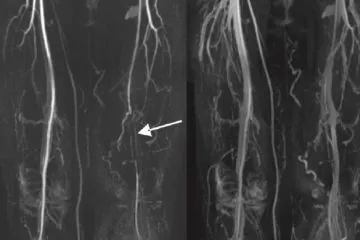

Nazywam się Michał Stelmachowski i od ponad 15 lat zajmuję się pracą nad naturalnymi rozwiązaniami pozwalającymi wyeliminować szereg uciążliwych, a także niebezpiecznych, dolegliwości związanych ze zbyt wysokim cholesterolem LDL, którego cząstki stopniowo zaklejają naczynia krwionośne niczym wosk, zmniejszając ich drożność, a co za tym idzie – blokując dopływ substancji odżywczych oraz tlenu do kluczowych tkanek i narządów, w tym mózgu i serca. Tego typu problemy często mają podłoże genetyczne, chociaż w wielu przypadkach to również wynik nieprawidłowej diety i zbyt małej ilości ruchu. Jedno jest pewne – jeśli odczuwamy dezorientację, zawroty głowy, szybką męczliwość, kłucie i dyskomfort w klatce piersiowej po wysiłku, wyziębienie i zasinienie nóg, świadczy to o tym, że niedokrwienność wkracza już w zaawansowane stadium.

Wiele osób sądzi, że podwyższony cholesterol to nic takiego, w końcu wiele osób taki ma. Wszystkie te osoby pragnę uświadomić, że taka sytuacja stopniowo doprowadza do upośledzonej przepustowości naczyń, a w konsekwencji do poważnych kłopotów zdrowotnych. Do tego dochodzą często bóle klatki piersiowej, szybka męczliwość po znikomym wysiłku, drętwienie rąk i nóg, pieczenie, obrzęki, zasinienie i „marmurkowa” skóra, a w najgorszych przypadkach nawet niewydolność narządów lub procesy martwicze. Wysoki cholesterol wymaga natychmiastowej reakcji.

Prowadzone badania wykazały, że działanie składników zawartych w formule Cariovico niemal natychmiast obniża „zły cholesterol”, czyli jego frakcję LDL, jednocześnie normalizując gospodarkę glukozowo-lipidową organizmu. Dzięki temu Cariovico minimalizuje odkładanie się blaszek miażdżycowych w tętnicach.

Przywrócenie prawidłowego profilu cukrowo-tłuszczowego organizmu jest niezwykle istotne, ale to nie wszystko. Cariovico posiada zdolność rozmiękczania, rozluźniania i – ostatecznie – stopniowego rozpuszczania nagromadzonych latami groźnych złogów w naczyniach krwionośnych. Są one w bezpieczny sposób wypłukiwane z organizmu.

Wysoka skuteczność preparatu Cariovico to zasługa najsilniejszych ekstraktów pochodzenia naturalnego, które w efekcie synergii nasilają nawzajem swoje właściwości. Formuła ta została okrzyknięta przełomem w naturalnej angiologii. To produkt inny od pozostałych, nieinwazyjnych metod – obniża zły cholesterol frakcji LDL, przywraca balans w profilu lipidowym organizmu, ułatwia naturalne oczyszczanie złogów lipidowych z naczyń krwionośnych, przywraca im elastyczność i wzmacnia je, minimalizując ryzyko zatorów i obrzęków.